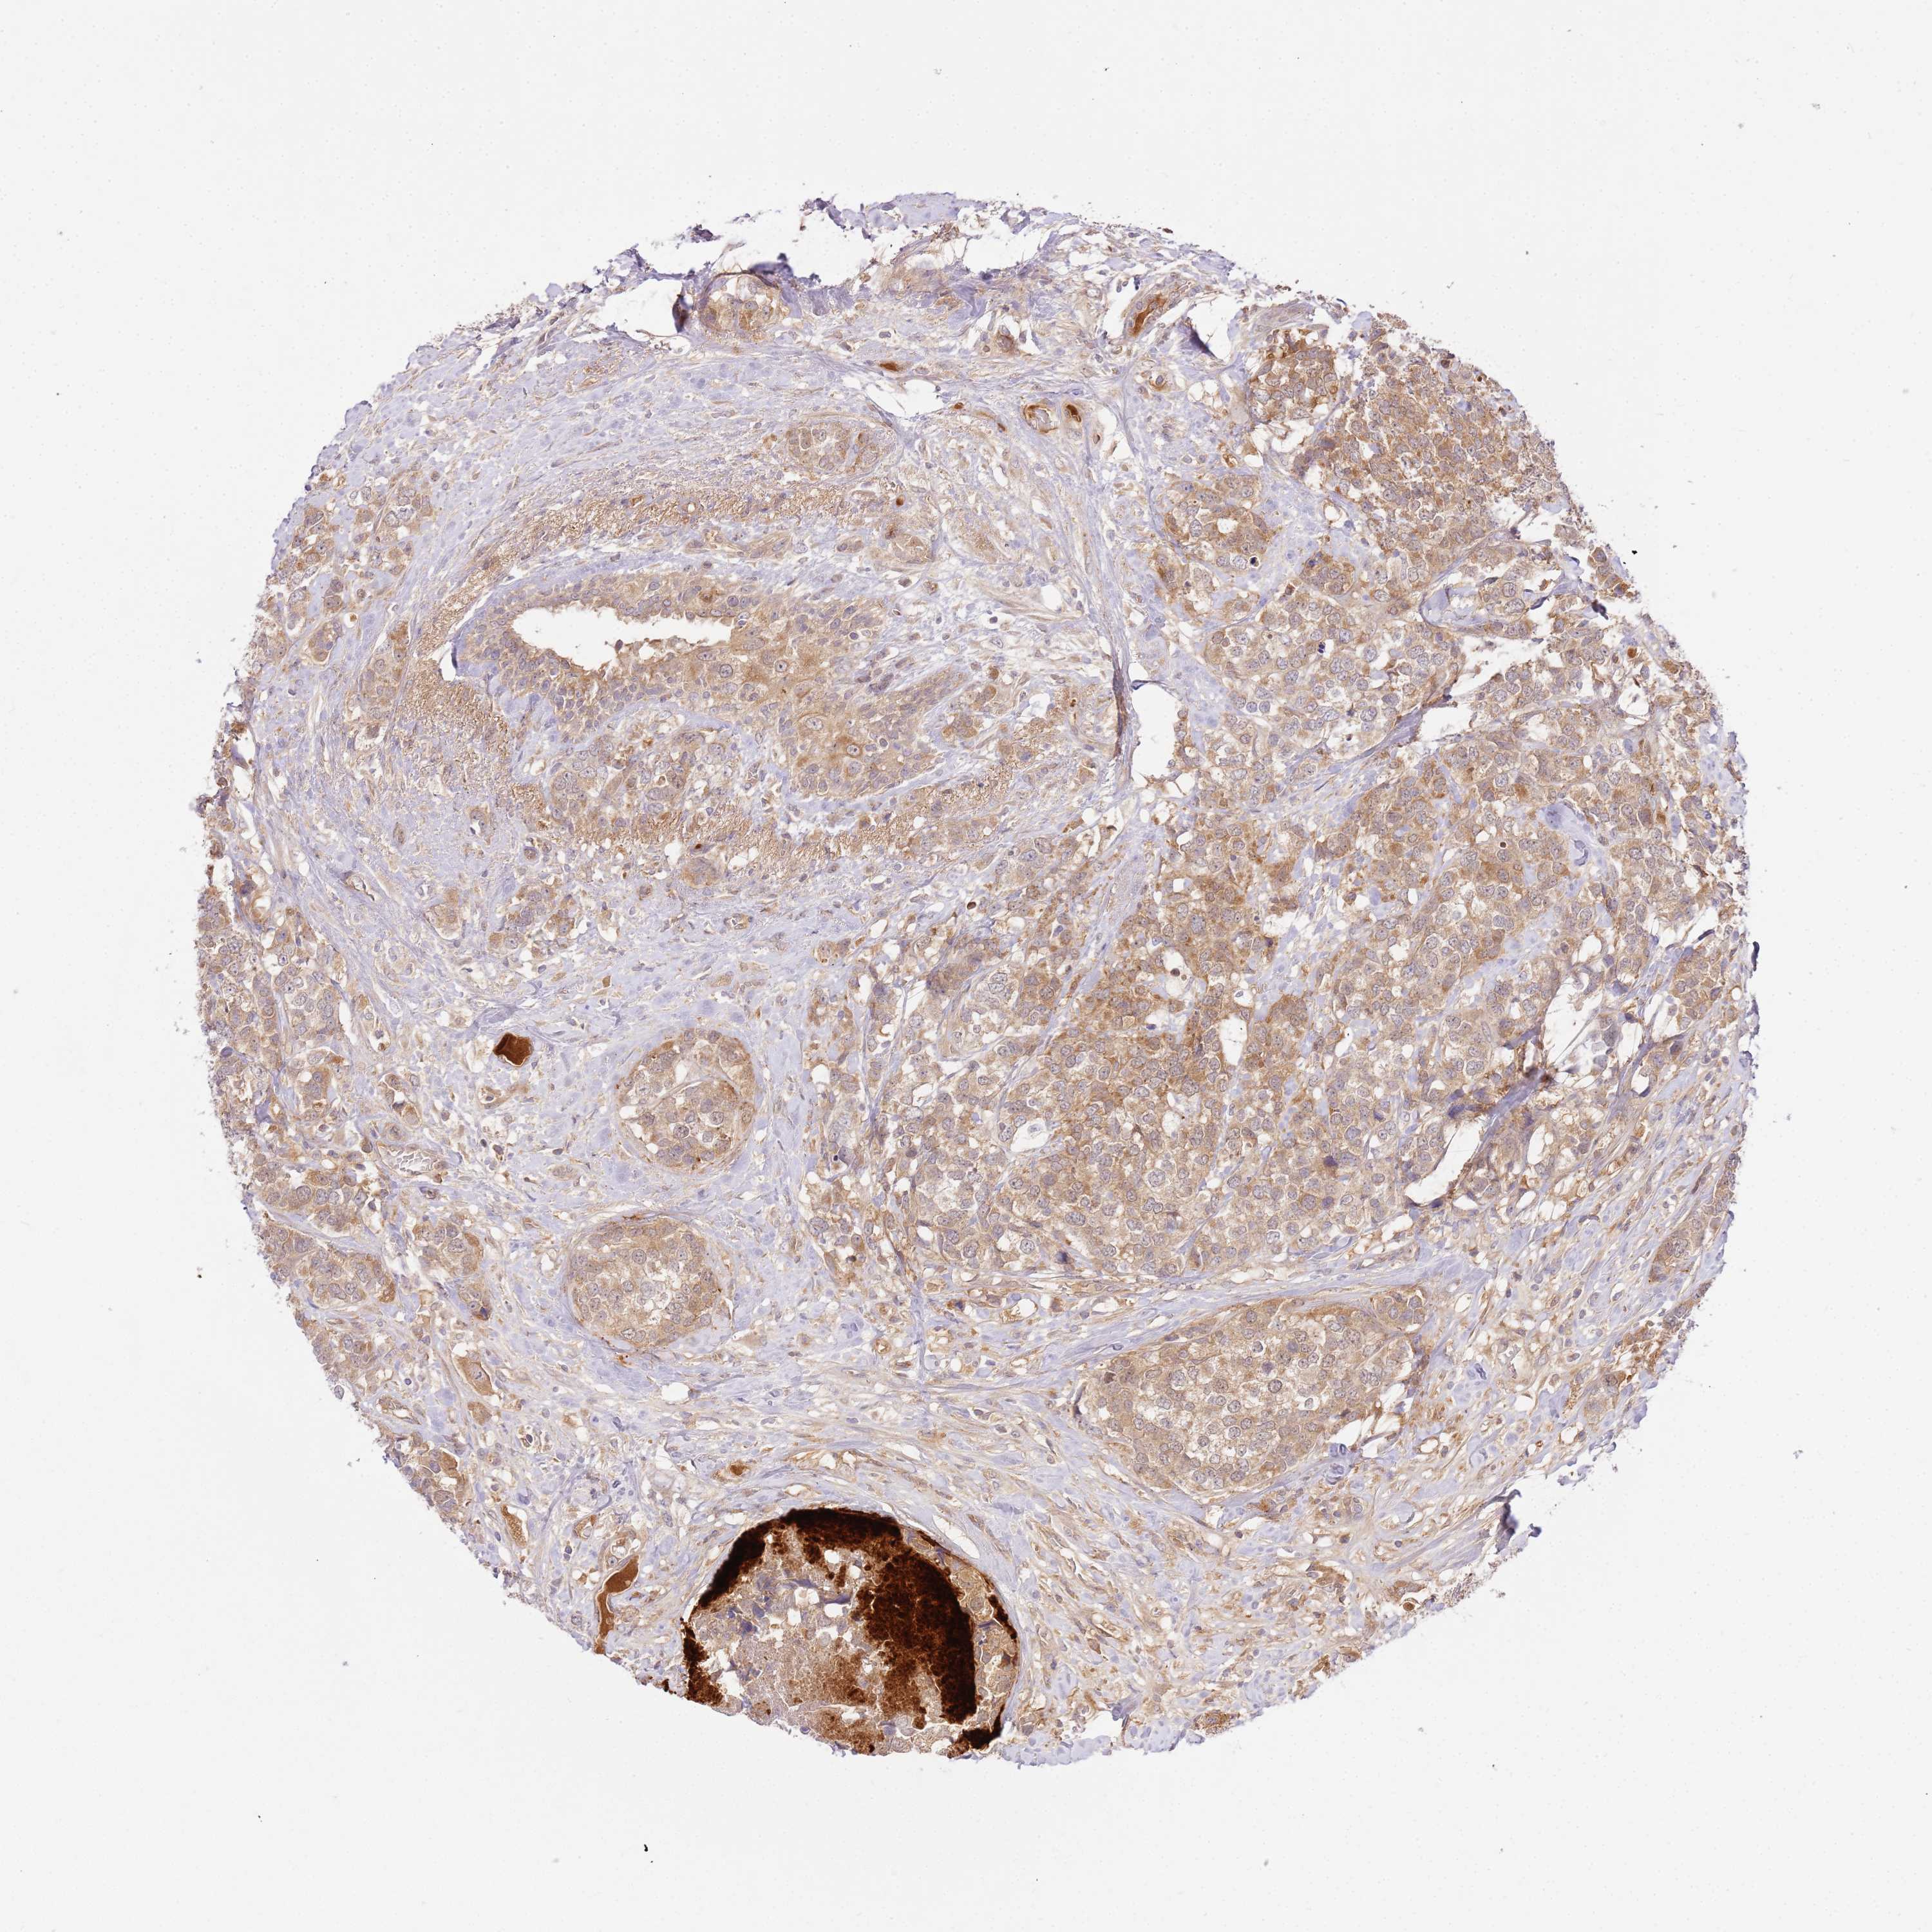

CANCER BREAST CANCER Show tissue menu

BRCA TCGA BRCA VALIDATION PROTEIN EXPRESSION